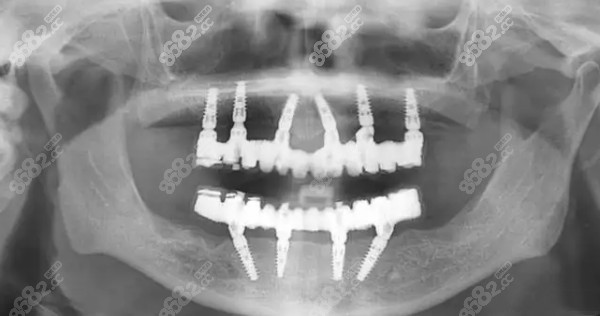

衡阳即刻负重半口种植牙价格:5-10万元左右

即刻负重技术是现在比较常用的种植牙技术,因为不用漫长的等待期~86/82,可以实现当天种牙,当天吃东西的愿望,因此还是蛮受欢迎的<cc。